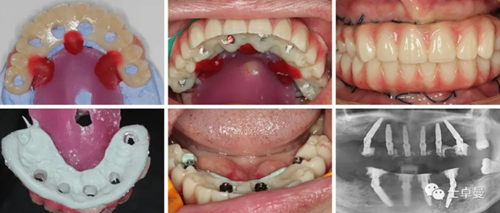

修復操作

術后放棄固位釘引導修復體就位,改用傳統(tǒng)的pick-up技術口內(nèi)粘接術前制作的臨時修復體;

術后2月,種植體完成骨結合,復查CBCT顯示種植體周圍骨穩(wěn)定,未見明顯邊緣骨吸收;

取下臨時修復體后口內(nèi)檢查,基臺周圍軟組織健康;

夾板開窗取印模,面弓轉移,復制臨時修復體頜位關系后設計CAD/CAM樹脂橋;

CAD/CAM樹脂橋戴入口內(nèi)后獲得了滿意的微笑曲線及軟組織側貌;

通過調(diào)整獲得了滿意的咬合關系,正中咬合時后牙保護前牙:雙側后牙均勻接觸,前牙輕接觸;

前伸及側方時前牙保護后牙:

前伸運動:前牙引導

側方運動:尖牙引導

夾板開窗加個性化托盤取最終印模,灌注石膏模型后在模型上制作石膏夾板,再將石膏夾板戴回口內(nèi)驗證模型精確度;

鈦支架口內(nèi)試戴及X線檢查;

永久修復體戴入后的口內(nèi)相及唇齒關系;